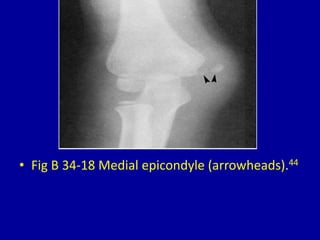

This document provides descriptions and images of avulsion injuries at various anatomical locations in the body. Avulsion injuries refer to the tearing away of a tendon, ligament, or muscle from the bone. The document lists 17 figures showing examples of avulsion injuries at locations such as the ischial tuberosity, anterior superior iliac spine, anterior inferior iliac spine, symphysis pubis, lesser trochanter, greater trochanter, fibular head, tibial eminence, posterior cruciate ligament, tibial tuberosity, inferior pole of the patella, calcaneal tuberosity, anterior and posterior capsule of the ankle joint, greater and lesser tuberosity of the